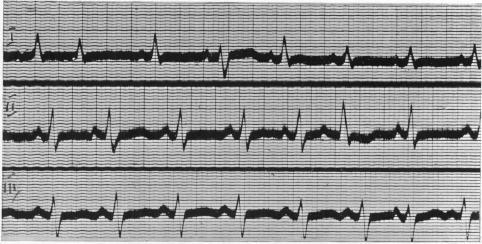

INCOMPLETE BUNDLE BRANCH BLOCK.

Br Heart J. 1944 Jul;6(3):139-48. doi: 10.1136/hrt.6.3.139.